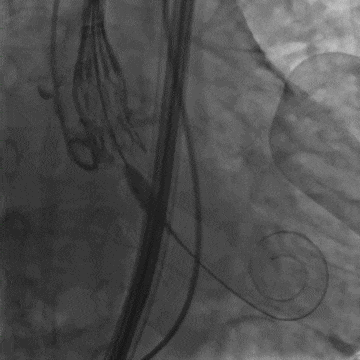

术中造影

全展开位造影

脱钩后造影